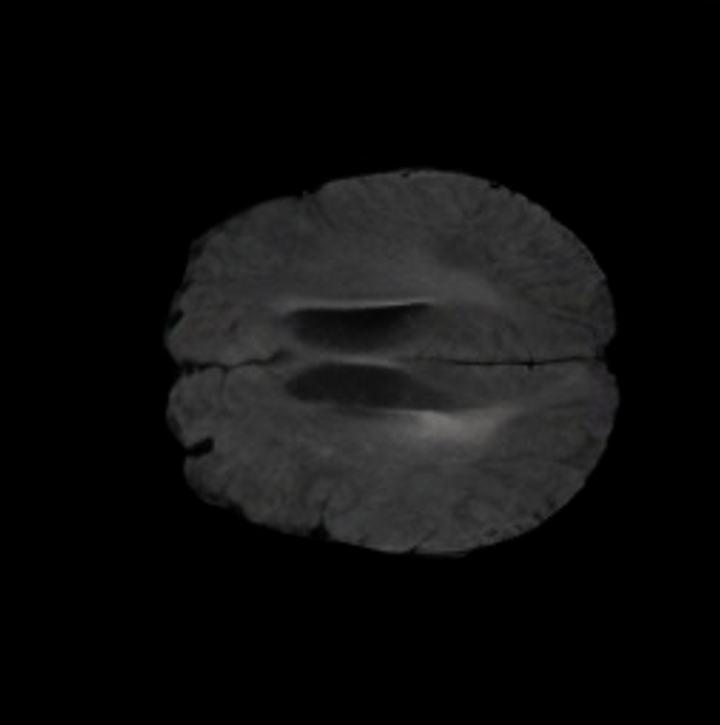

Brain Volumes Preservation. The generated MRIs by our X-Diffusion retain almost the exact same average brain volume vs. of the real MRIs.

Tumour Information Preservation. For the brain tumor segmentation, we use a Swin UNETR model[28, 70], trained with random rotation, and intensity as data augmentation. On the test set with human ground-truth annotations (), the brain volumes generated from single slice input preserve the volume of the different tumour components (paired t-test, for all 3 classes). In Figure 4, we highlight the tumor profiles of the generated MRIs compared to the ground truth tumour profile. The real MRI Dice score in the test set is 85.15 while the generated MRIs from a single slice have a dice score of 83.09. This shows how the generated MRIs indeed preserve the tumor information and can act as an affordable and informative pseudo-MRI, before conducting an actual costly MRI examination in hospitals. More detailed results are provided in supplementary material.

B.2 Brain Volumes Preservation

The comparison of generated MRIs versus reference MRIs suggest a nearly perfect preservation of brain volume (in mm3) with median volume of reference MRIs of versus generated MRIs (see an example of brain generation in Figure II).

On the test set with human ground-truth annotations (), the brain volumes generated from single slice input preserve the volume of the different tumour components (paired t-test, for all 3 classes) (see Table I). The real MRI Dice scores are put for reference to our generated MRIs. X-Diffusion outperforms baselines TPDM [39] and ScoreMRI [19] in tumour preservation (see Table I and Figure III). We ran experiments comparing the tumour segmentation Dice Score varying X-Diffusion configurations. The multi-slice input X-Diffusion achieves marginally better Dice Score than the single slice input model (83.47 83.09). We also ran experiments with slice input used for volume reconstruction intersecting or not with tumour. We observe on average a drop of 6% Dice Score (see Table I). Further away from the tumour the input slice for volume reconstruction is selected, we observe a linear decrease in tumour segmentation Dice Score with lowest value of 77.21 Dice Score (see Figure VI).